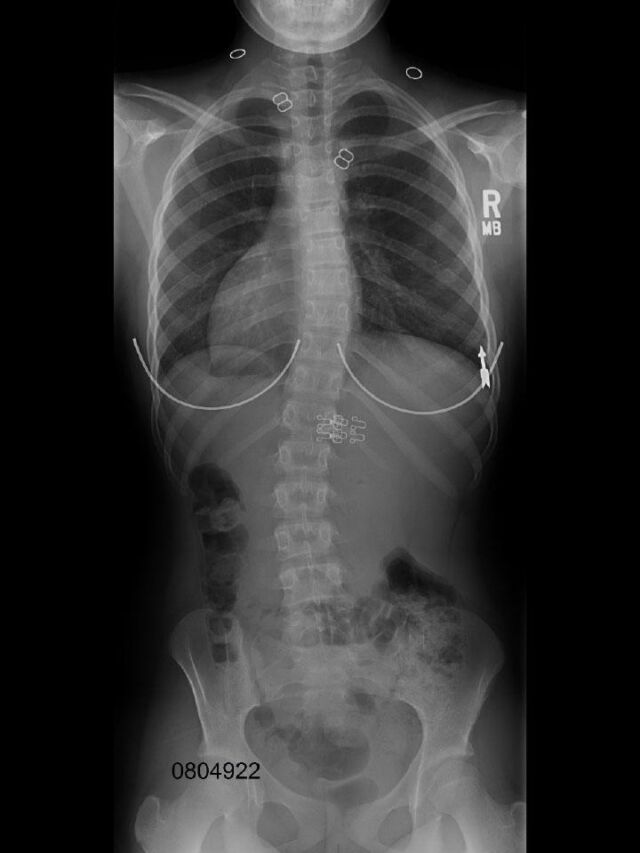

Based on the patient's X-rays, the observed spinal curve pattern determines the specific design of the pads and expansion spaces. The brace is fabricated custom to scan or cast and is custom fit for each individual patient.

The SCT 3D Chêneau (Style) brace is a 3D corrective orthosis able to provide excellent in-brace correction as well as radiological and cosmetic end results.